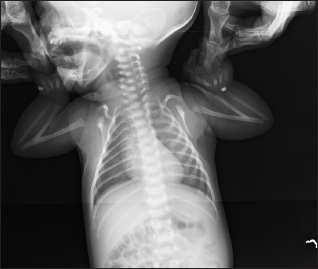

Neonatal Intestinal Obstruction: A Case of Jejunal and Colonic Atresia with Micro Colon

Dr. Suwaid Mohammad Abba, Anas Ismail, Dambatta Abdullahi Hamisu (Author)

14-16